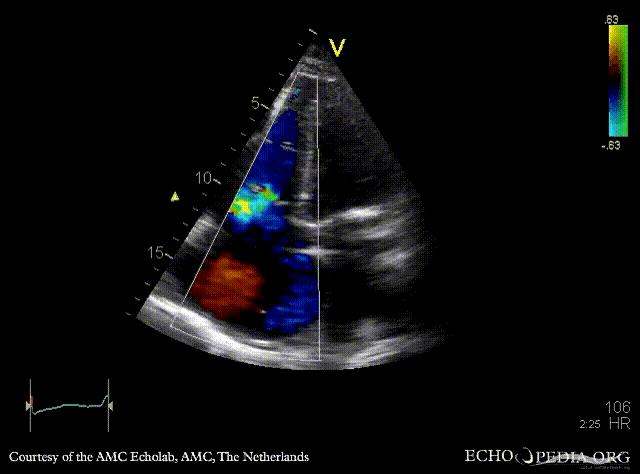

A4CH with Color Doppler: severe tricuspid regurgitation